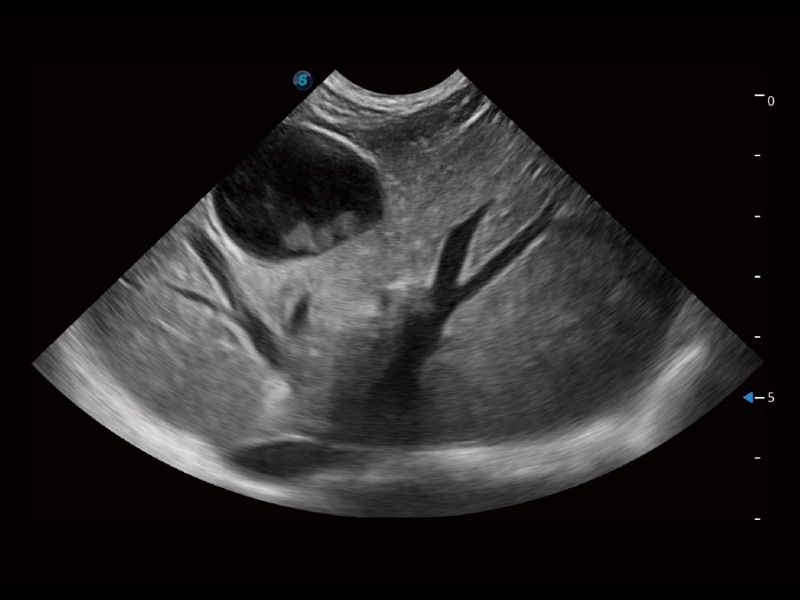

大型犬、马科、农场动物及大型异宠动物

为精细结构及组织边缘提供高清晰度的图像和更大的成像视野。帮助减轻医生的用眼疲劳,快速精准获得测量的数据。

提供解剖示意图、标准超声图像、扫查手法图和操作者实时检查图像,指导操作者进行标准切面的正确扫查。